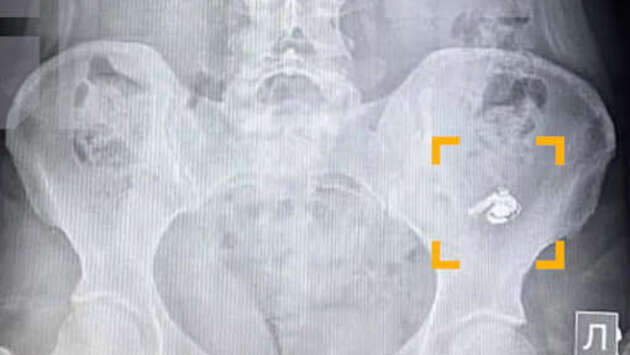

Жительница Уфы по ошибке проглотила беспроводной наушник AirPods, перепутав его с таблеткой. Инцидент произошел, когда девушка сложила наушники в карман рядом с лекарствами и во время приема препаратов не стала смотреть, что именно кладет в рот. Об этом сообщает издание Life.ru со ссылкой на Telegram-канал SHOT. По словам уфимки по имени Мария, в момент глотания она почувствовала дискомфорт, но решила, что ей попалась крупная таблетка. Позже, обнаружив пропажу одного из наушников, девушка обратилась за медицинской помощью. В больнице ей сделали рентген, который подтвердил наличие инородного предмета в желудке. Врачи решили не извлекать наушник, чтобы не спровоцировать осложнения, и рекомендовали дождаться его естественного выхода. Пациентку отпустили домой под наблюдение. Как рассказала Мария, устройство продолжало работать – при включении музыка воспроизводилась, однако услышать ее было невозможно. Спустя сутки наушник самостоятельно покинул организм, пройдя из желудка в кишечник. После случившегося девушка пообещала впредь быть внимательнее при приеме лекарств.